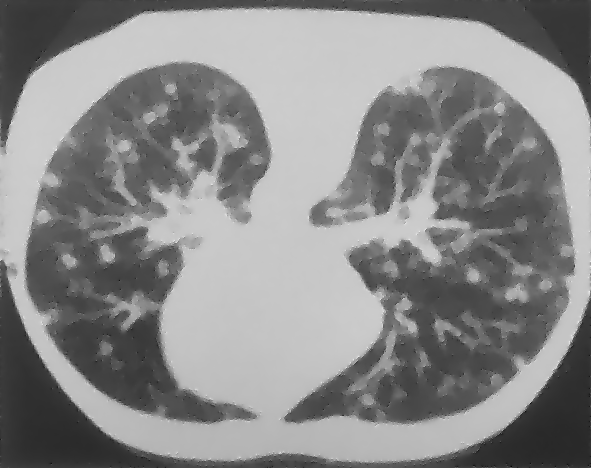

Example 2: restoration of images corrupted by blur and SPN or AWLN. In this example we evaluate the performance of the proposed TV-L1 model on three medical test images lungs (), Fig. 5 (a), ecography (), Fig. 6 (a), and aneurism (), Fig. 7 (a), synthetically corrupted by Gaussian blur of parameters band=5 and sigma=1 and by two types of impulsive noise, namely SPN and AWLN.

First, for what concerns corruptions by SPN, in Figs. 5, 6, 7 we report for the three considered test images the original and corrupted image together with the estimated -maps in the first column (with the size of the neighborhoods used for the -maps estimation reported in the captions), the restoration results, obtained by the four compared methods, in the second column (with the achieved ISNR values in the captions) and a zoomed detail of the restored images - green- bordered in Figs. 5 (a), 6 (a), 7 (a) - in the last column.

The reported ISNR values as well as the visual inspection of the restored images and of the zoomed details strongly indicate how the proposed space-variant regularizer allows for higher quality restorations. In particular, it is worth remarking how, with respect to the space-variant TV model, the additional degrees of freedom represented by the scale parameters used in our proposal, yield a sufficient additional flexibility for avoiding unwanted spurious effects - see, e.g., spikes in Figs. 5 (i), 6 (i), 7 (i).

In the second part of this example, we consider the restoration of the same three medical test images corrupted by the same blur of parameters

band=5 , sigma=1 and by a different impulsive noise, namely AWLN of level yielding BSNR=10. In Table 2 we report the ISNR values achieved by the compared methods and in Fig. 8 we show the original images, the corrupted images and the restored images by our model.

The results in Table 2 confirm that, also in case of images corrupted by AWLN, the proposed TV-L1 model outperforms

its competitors in terms of ISNR. Moreover, the restored images depicted in the last column of Fig. 8 provide further evidence of the good quality restorations achievable by our proposal.

![]() |

| (a) original | (b) original | (c) original |

| (d) corrupted (BSNR=10) | (e) corrupted (BSNR=10) | (f) corrupted (BSNR=10) |

| (g) TV-L1 | (h) TV-L1 | (i) TV-L1 |

| TV-L1 | TVp-L1 | TV-L1 | TV-L1 | |

|---|---|---|---|---|

| lungs | 6.20 | 6.80 | 7.30 | 7.85 |

| ecography | 5.93 | 6.40 | 7.88 | 8.32 |

| aneurism | 9.10 | 9.44 | 10.13 | 10.70 |